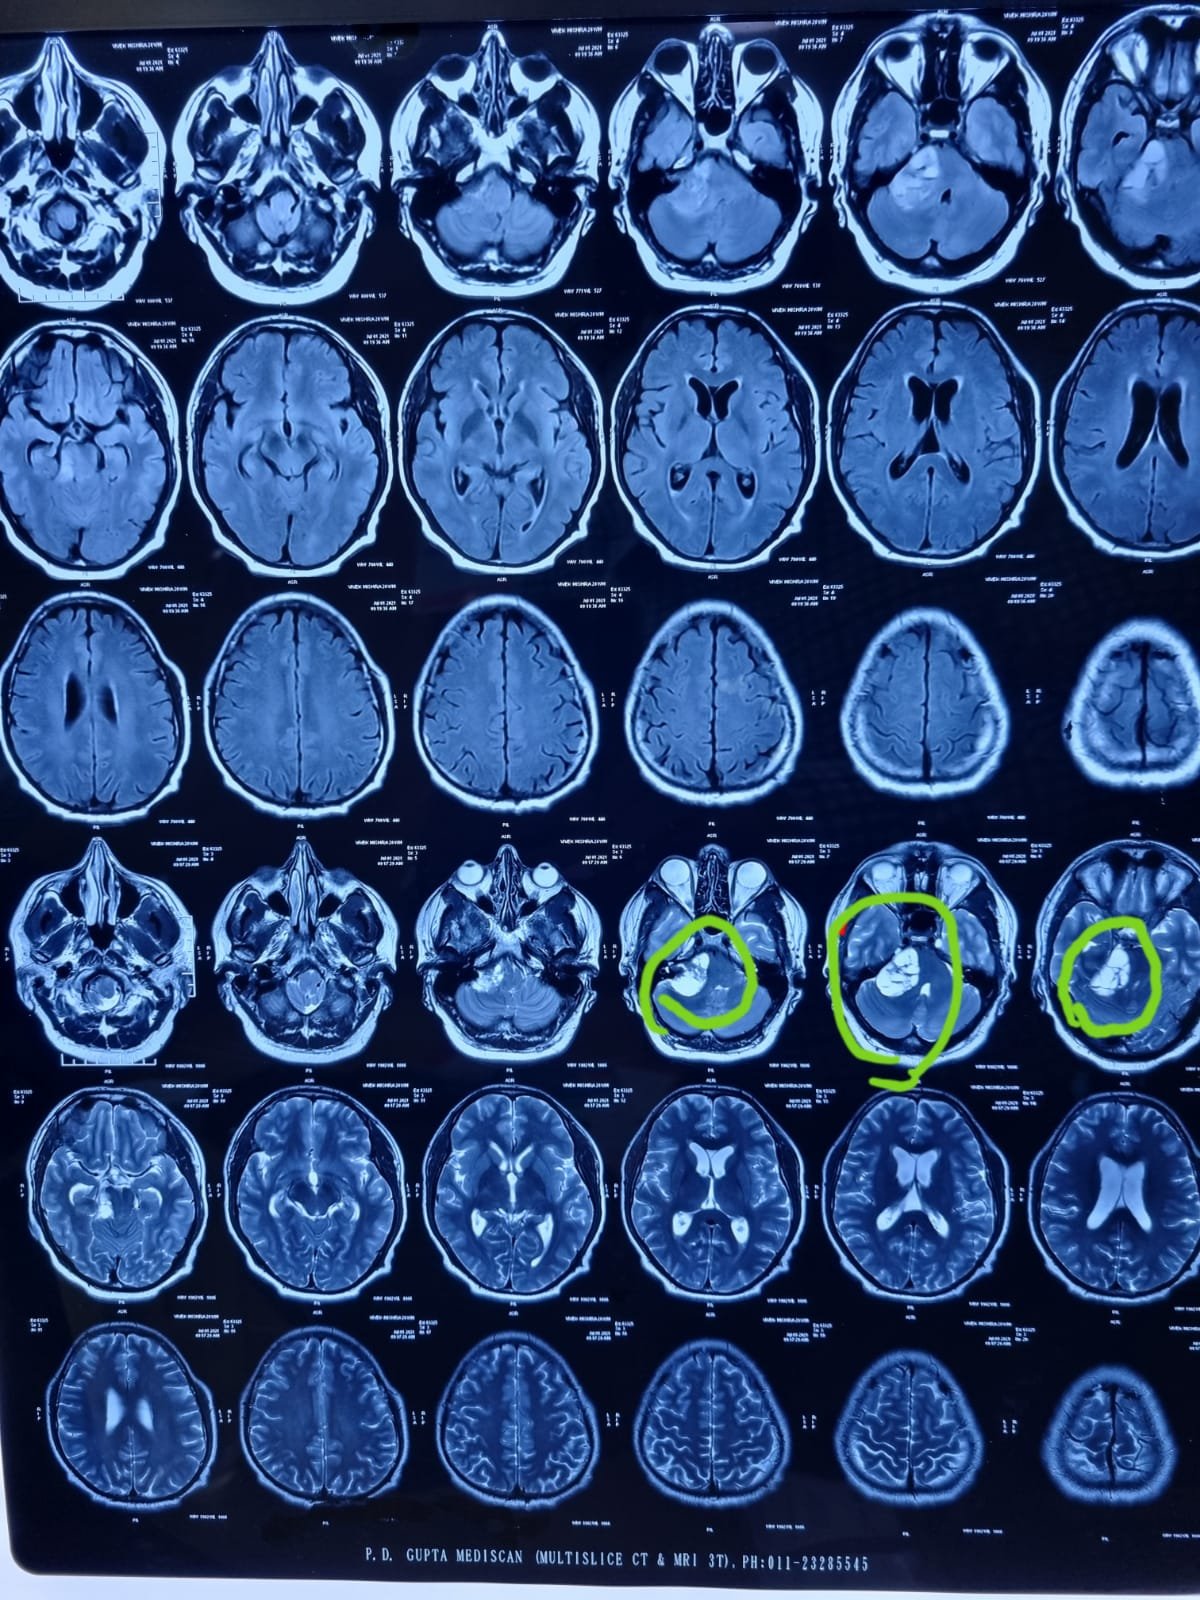

अजब करने वाली घटना

वोक्हार्ट अस्पताल में एक इंजिनियर के दाहिने कान से निकाला ५० ग्राम ट्यूमर मिरारोड – मिरारोड के वोक्हार्ट  अस्पताल में २० वर्षीय एक इंजिनियर के दाहिने कान से ५० ग्राम का ट्यूमर...

वॉक्हार्ट अस्पताल द्वारा पक्षाघात के बारे में जागरूकता...

पिछले दो साल में अब तक २३० स्ट्रोक मरीजों का इलाज मिरारोड :- स्ट्रोक के बारे में जागरूकता निर्माण करने के लिए वॉक्हार्ट अस्पताल द्वारा सर्व्हायव्ह ग्रुप बनाकर एक विशेष परिसंवाद का आयोजन...